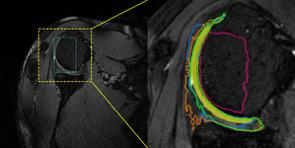

Accurate magnetic resonance imaging (MRI) segmentation is crucial for clinical decision-making, but remains labor-intensive when performed manually. Convolutional neural network (CNN)-based methods can be accurate and efficient, but often generalize poorly to MRI's variable contrast, intensity inhomogeneity, and protocols. Although the transformer-based Segment Anything Model (SAM) has demonstrated remarkable generalizability in natural images, existing adaptations often treat MRI as another imaging modality, overlooking these modality-specific challenges. We present SAMRI, an MRI-specialized SAM trained and validated on 1.1 million labeled MR slices spanning whole-body organs and pathologies. We demonstrate that SAM can be effectively adapted to MRI by simply fine-tuning its mask decoder using a two-stage strategy, reducing training time by 94% and trainable parameters by 96% versus full-model retraining. Across diverse MRI segmentation tasks, SAMRI achieves a mean Dice of 0.87, delivering state-of-the-art accuracy across anatomical regions and robust generalization on unseen structures, particularly small and clinically important structures.